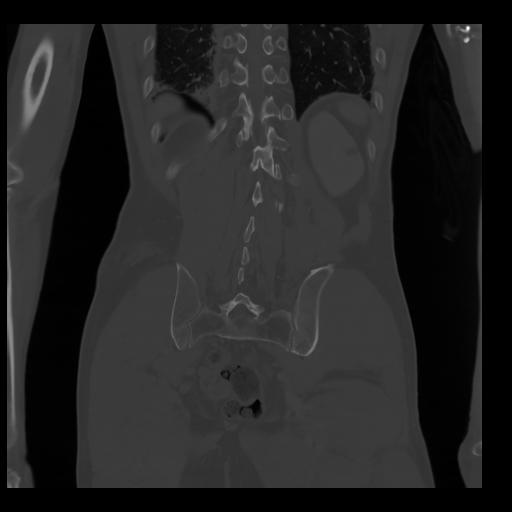

35 CUERPO,CE,Coronal,3.000,CUERPO,Coronal,